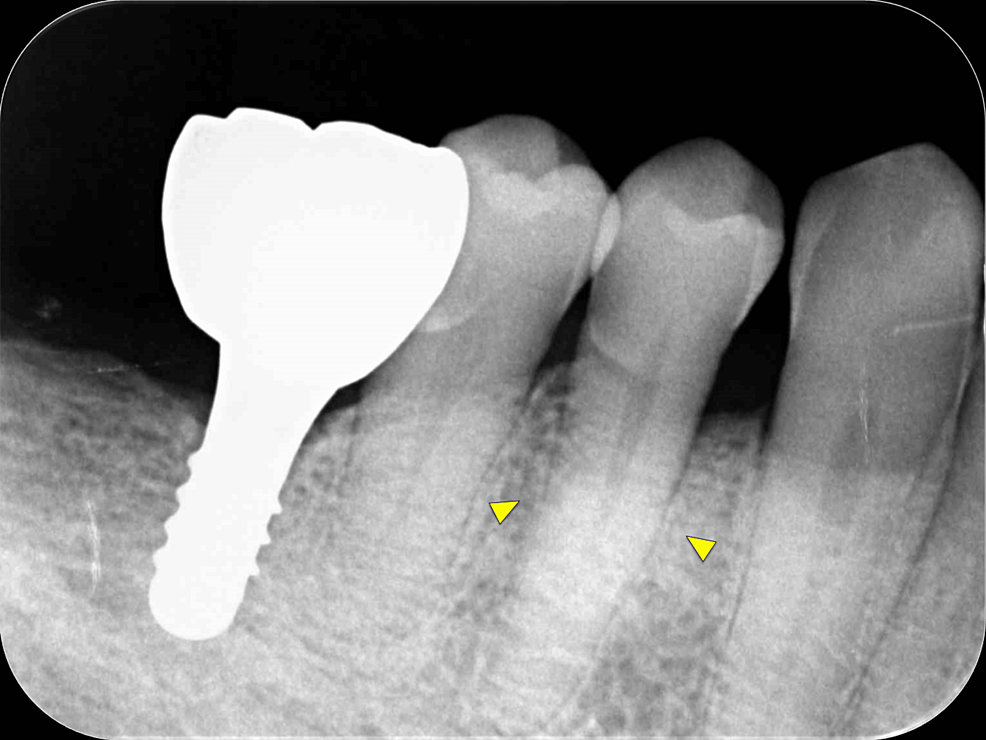

First, initial treatment including oral hygiene instruction was provided, followed by scaling and root planing. Teeth #16, #27, #37, and #46 were extracted, as they were considered too difficult to preserve. After reevaluation, a dental implant was provided for tooth #46. The patient was enrolled in supportive periodontal therapy after it was confirmed that the initial course of periodontal treatment had stabilized conditions. Subsequently, an acute periodontal abscess was observed in #44, however, requiring the start of anti-inflammatory treatment including periodontal pocket curettage under local anesthesia and oral antibiotics. Nevertheless, no improvement was found in the 6-mm buccal pocket of #44, so periodontal tissue regeneration therapy was planned. Before starting such treatment, in addition to intraoral radiography, cone-beam computed tomography (CBCT) was also performed using the 3DX Multi Image Micro CT (J MORITA Co., Ltd., Kyoto, Japan) (Figures 1, 2). The scan parameters were as follows: 90-kV tube voltage; 7-mA tube current; field of view, 60 mm x 60 mm; and slice thickness, 0.125 mm. The CBCT images revealed an intrabony, two-walled, defect around #44 that was slightly less radiolucent on the intraoral radiographic image. It was localized on the buccal side from the proximal to the distal aspect. A relatively large mandibular torus interior was also observed on the lingual side of #44 and #43.

Intraoral radiography and CBCT scanning were performed 14 months postoperatively (Figures 4, 5). The results were displayed on a personal computer monitor screen, and the morphology of the bone at the surgical site and its internal structure was observed in 3D, by which the regrowth of bone-like structures at the site of the intrabony defect was confirmed. At two years postoperatively, no subjective symptoms such as pain or objective signs such as tooth movement or gingival recession were observed. No other notable findings or abnormalities were observed, and the postoperative course was judged to be good.